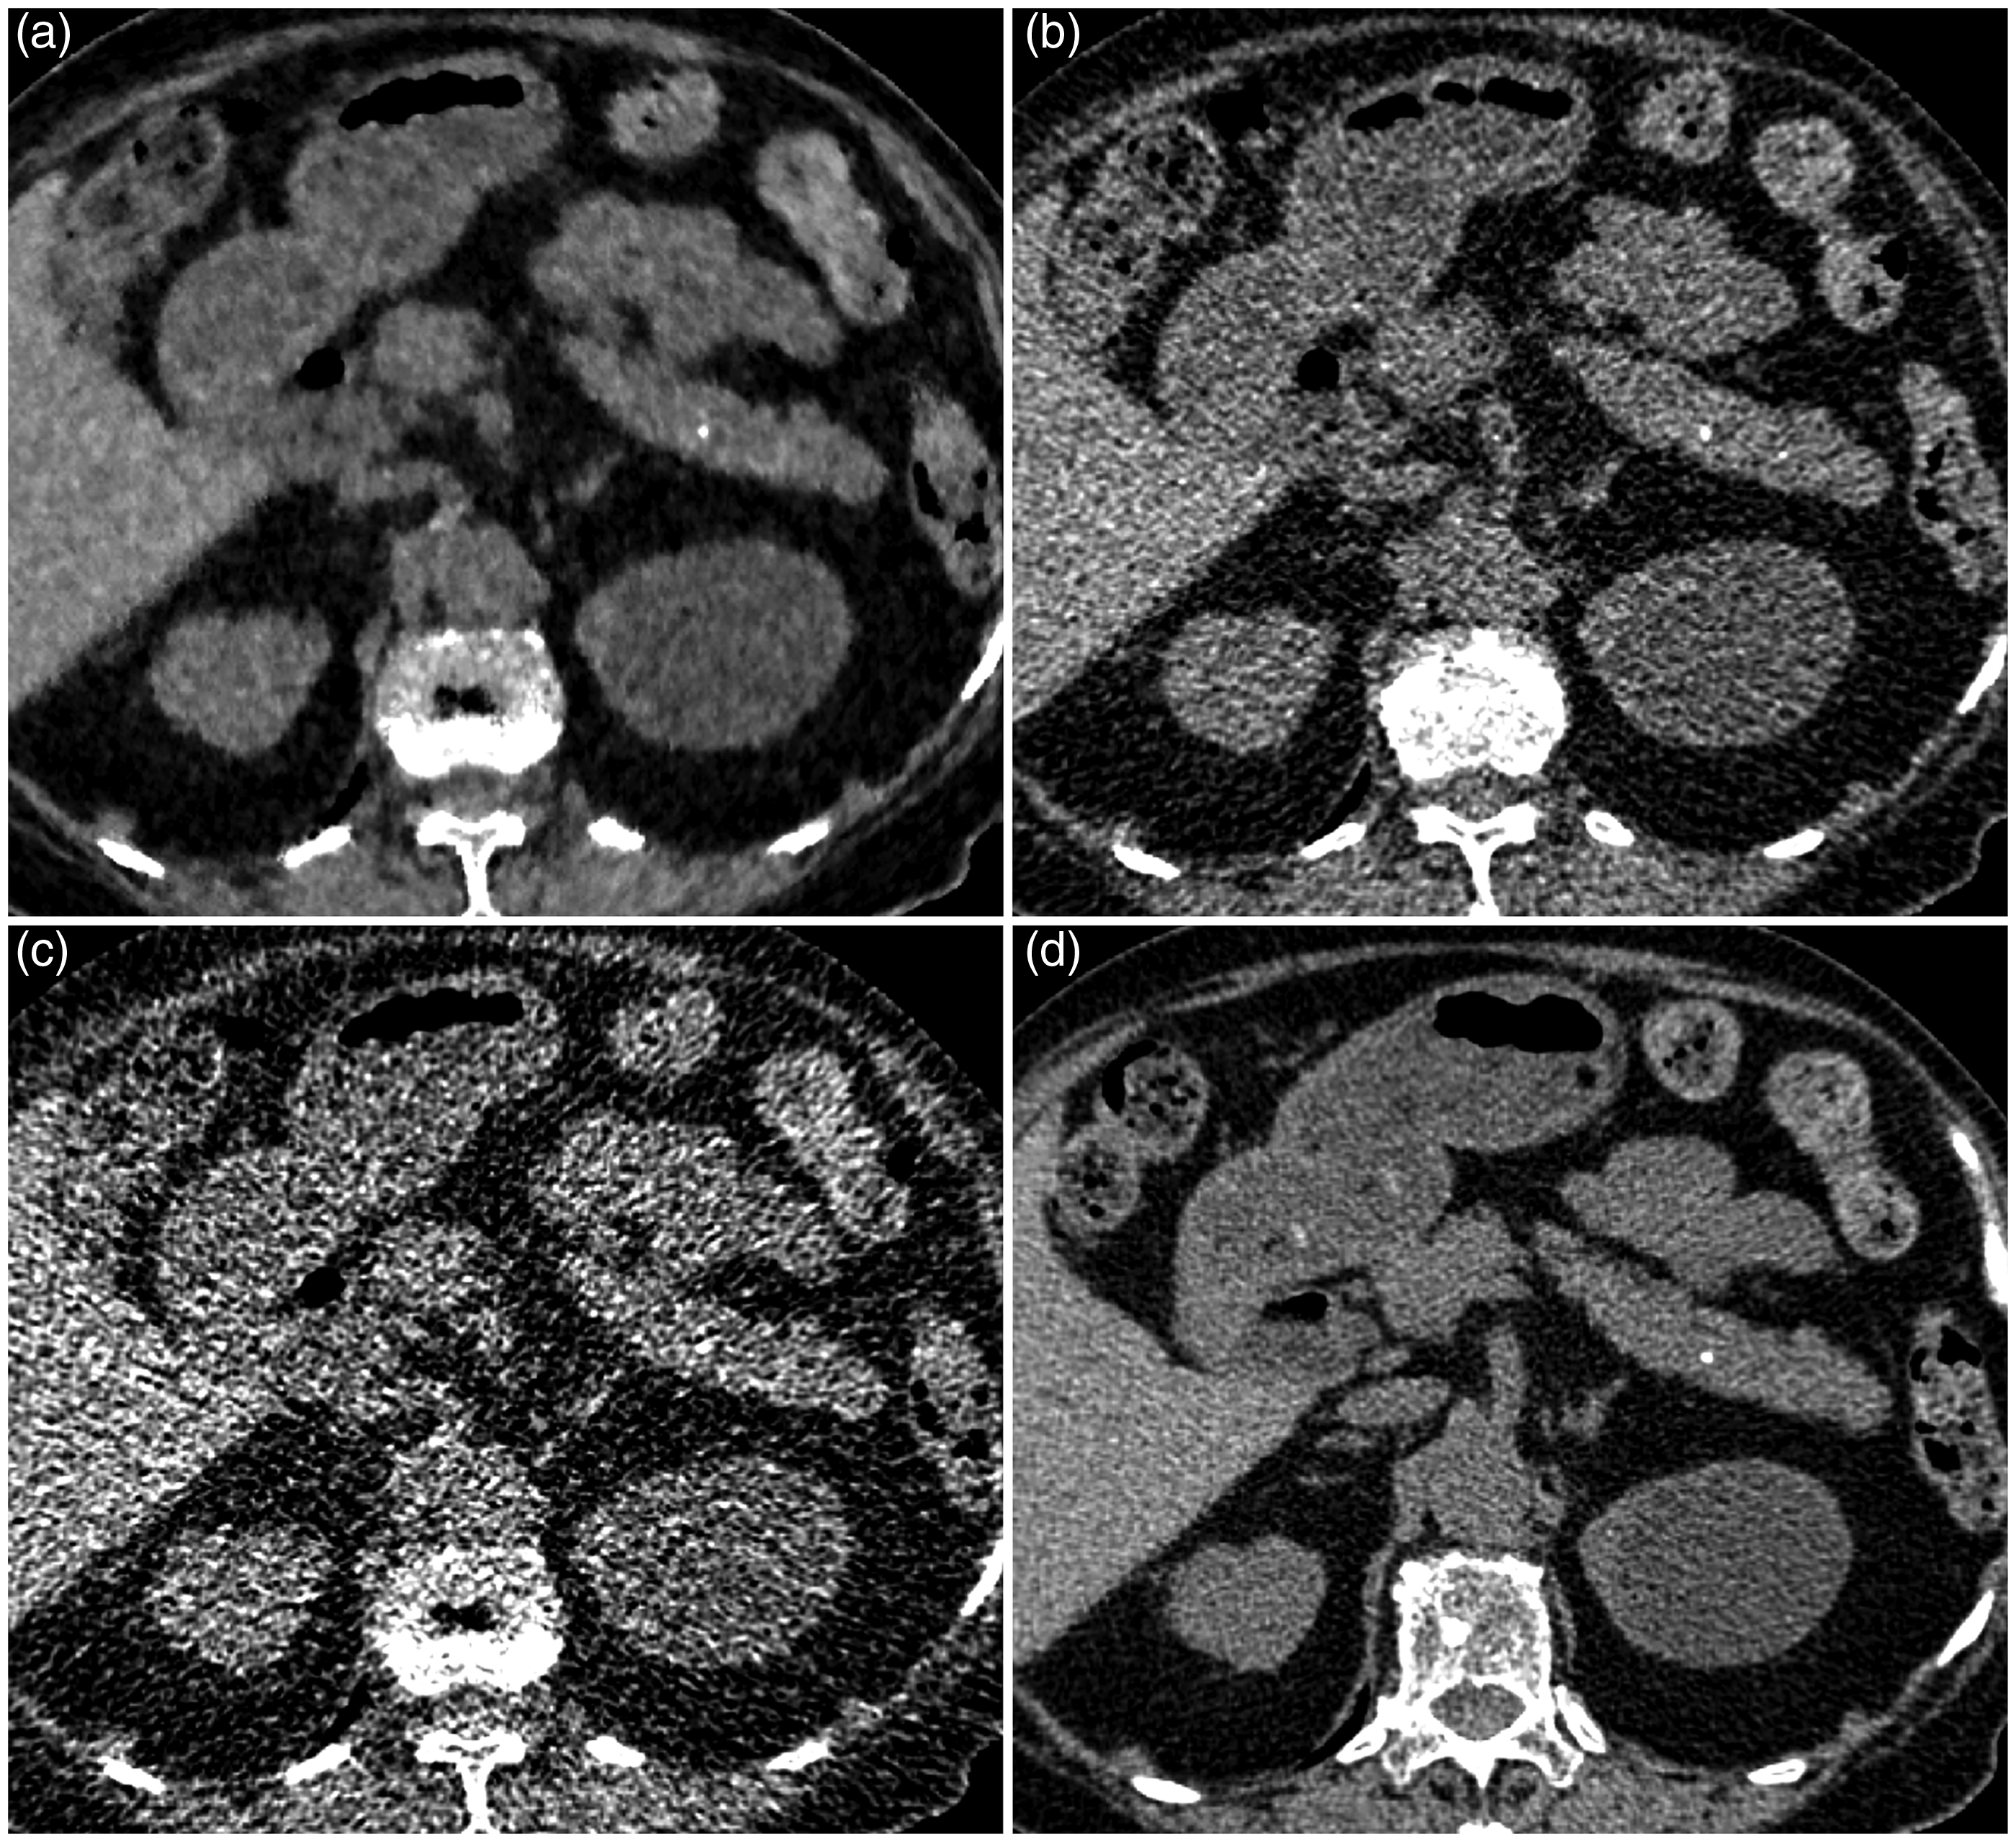

Nine patients had pancreatic calcification (Fig. 1). The location of the calcification was clear in all cases. The details of pancreatic calcifications are described in Table 1. The actual certainty score for the presence of pancreatic calcification by each reader is summarized in Table 2. With UL-ASIR, many cases were evaluated as 3 (presence equivocal) by both readers. The inter-observer agreement was fair (κ = 0.381), and the intra-observer agreement was fair to moderate (κ = 0.264 for reader 1 and κ = 0.418 for reader 2).

Axial unenhanced CT images of UL-MBIR (a), L-ASIR (b), UL-ASIR (c), and R-FBP (d) of an 82-year-old woman weighing 44 kg. Pancreatic calcification (3 mm diameter) is clearly depicted on UL-MBIR. On UL-MBIR/L-ASIR/UL-ASIR, it was evaluated as 4 (calcification probably present)/2 (calcification probably not present)/3 (calcification presence equivocal) by reader 1 and 4/3/3 by reader 2. Characteristics of pancreatic calcifications. Pb, pancreatic body; Ph, pancreatic head; Pt, pancreatic tail. Actual evaluation scores for each reconstruction method. Scores indicate the followings: 5, calcification definitely present; 4, calcification probably present; 3, calcification presence equivocal; 2, calcification probably not present; 1, no calcification.